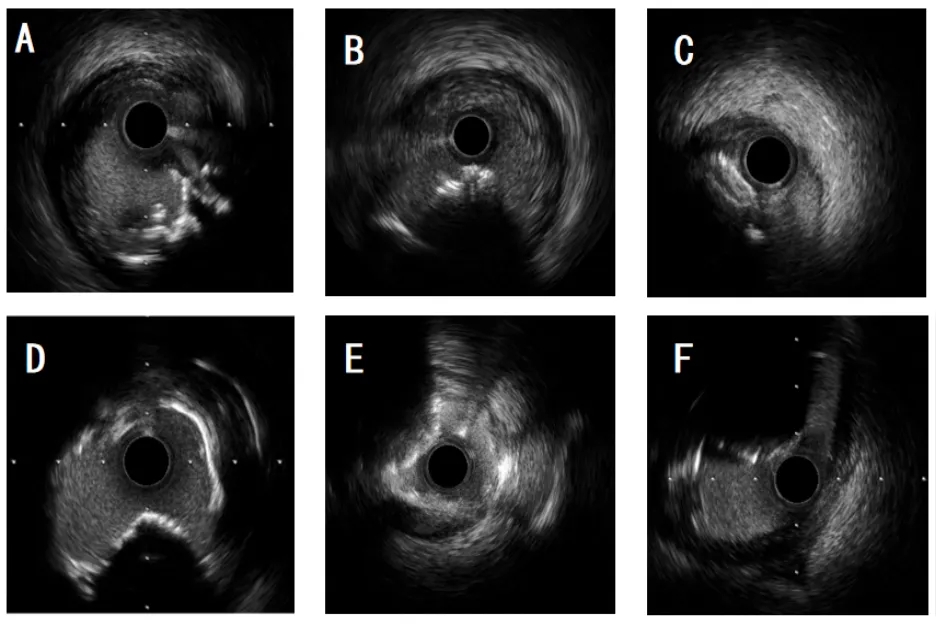

普通IVUS可见强回声伴声影,高分辨率IVUS(HD-IVUS)可判断纤维帽是否连续,区分爆发型(破裂)与非爆发型(完整)。

图7.IVUS可显示和区别不同类型的钙化病变。A和B为爆发型钙化结节,在IVUS上表现为凸入管腔的不规则簇状钙化团块,表面不规则,常伴强后方声影和可能血栓低回声信号。C-F为各种形态的非爆发型钙化结节,在IVUS上表现为凸入管腔的团块状或盘状钙化,表面相对光滑、纤维帽较完整,后方伴声影但无明显簇状不规则结构。(IVUS设备:Boston Scientific OptiCross HD 60MHz)

光学相干断层成像

光学相干断层扫描(OCT)是诊断CN的金标准,分辨率高。爆发型CN表现为表面不规则、纤维帽破裂、血栓覆盖。非爆发型CN则表面光滑、纤维帽完整。

图8.OCT可显示和区别不同类型的钙化病变。A-D为各种形态的非爆发型钙化结节,在OCT上的表现为凸入管腔的钙化团块,表面相对光滑、覆盖完整纤维帽,无血栓附着,但伴强信号衰减。E-F为爆发型钙化结节,在OCT上OCT上表现为凸入管腔的不规则高背散射钙化团块,表面不规则、纤维帽破裂,常伴有附壁血栓和强信号衰减。(OCT设备:Abbott Dragonfly OpStar™ )